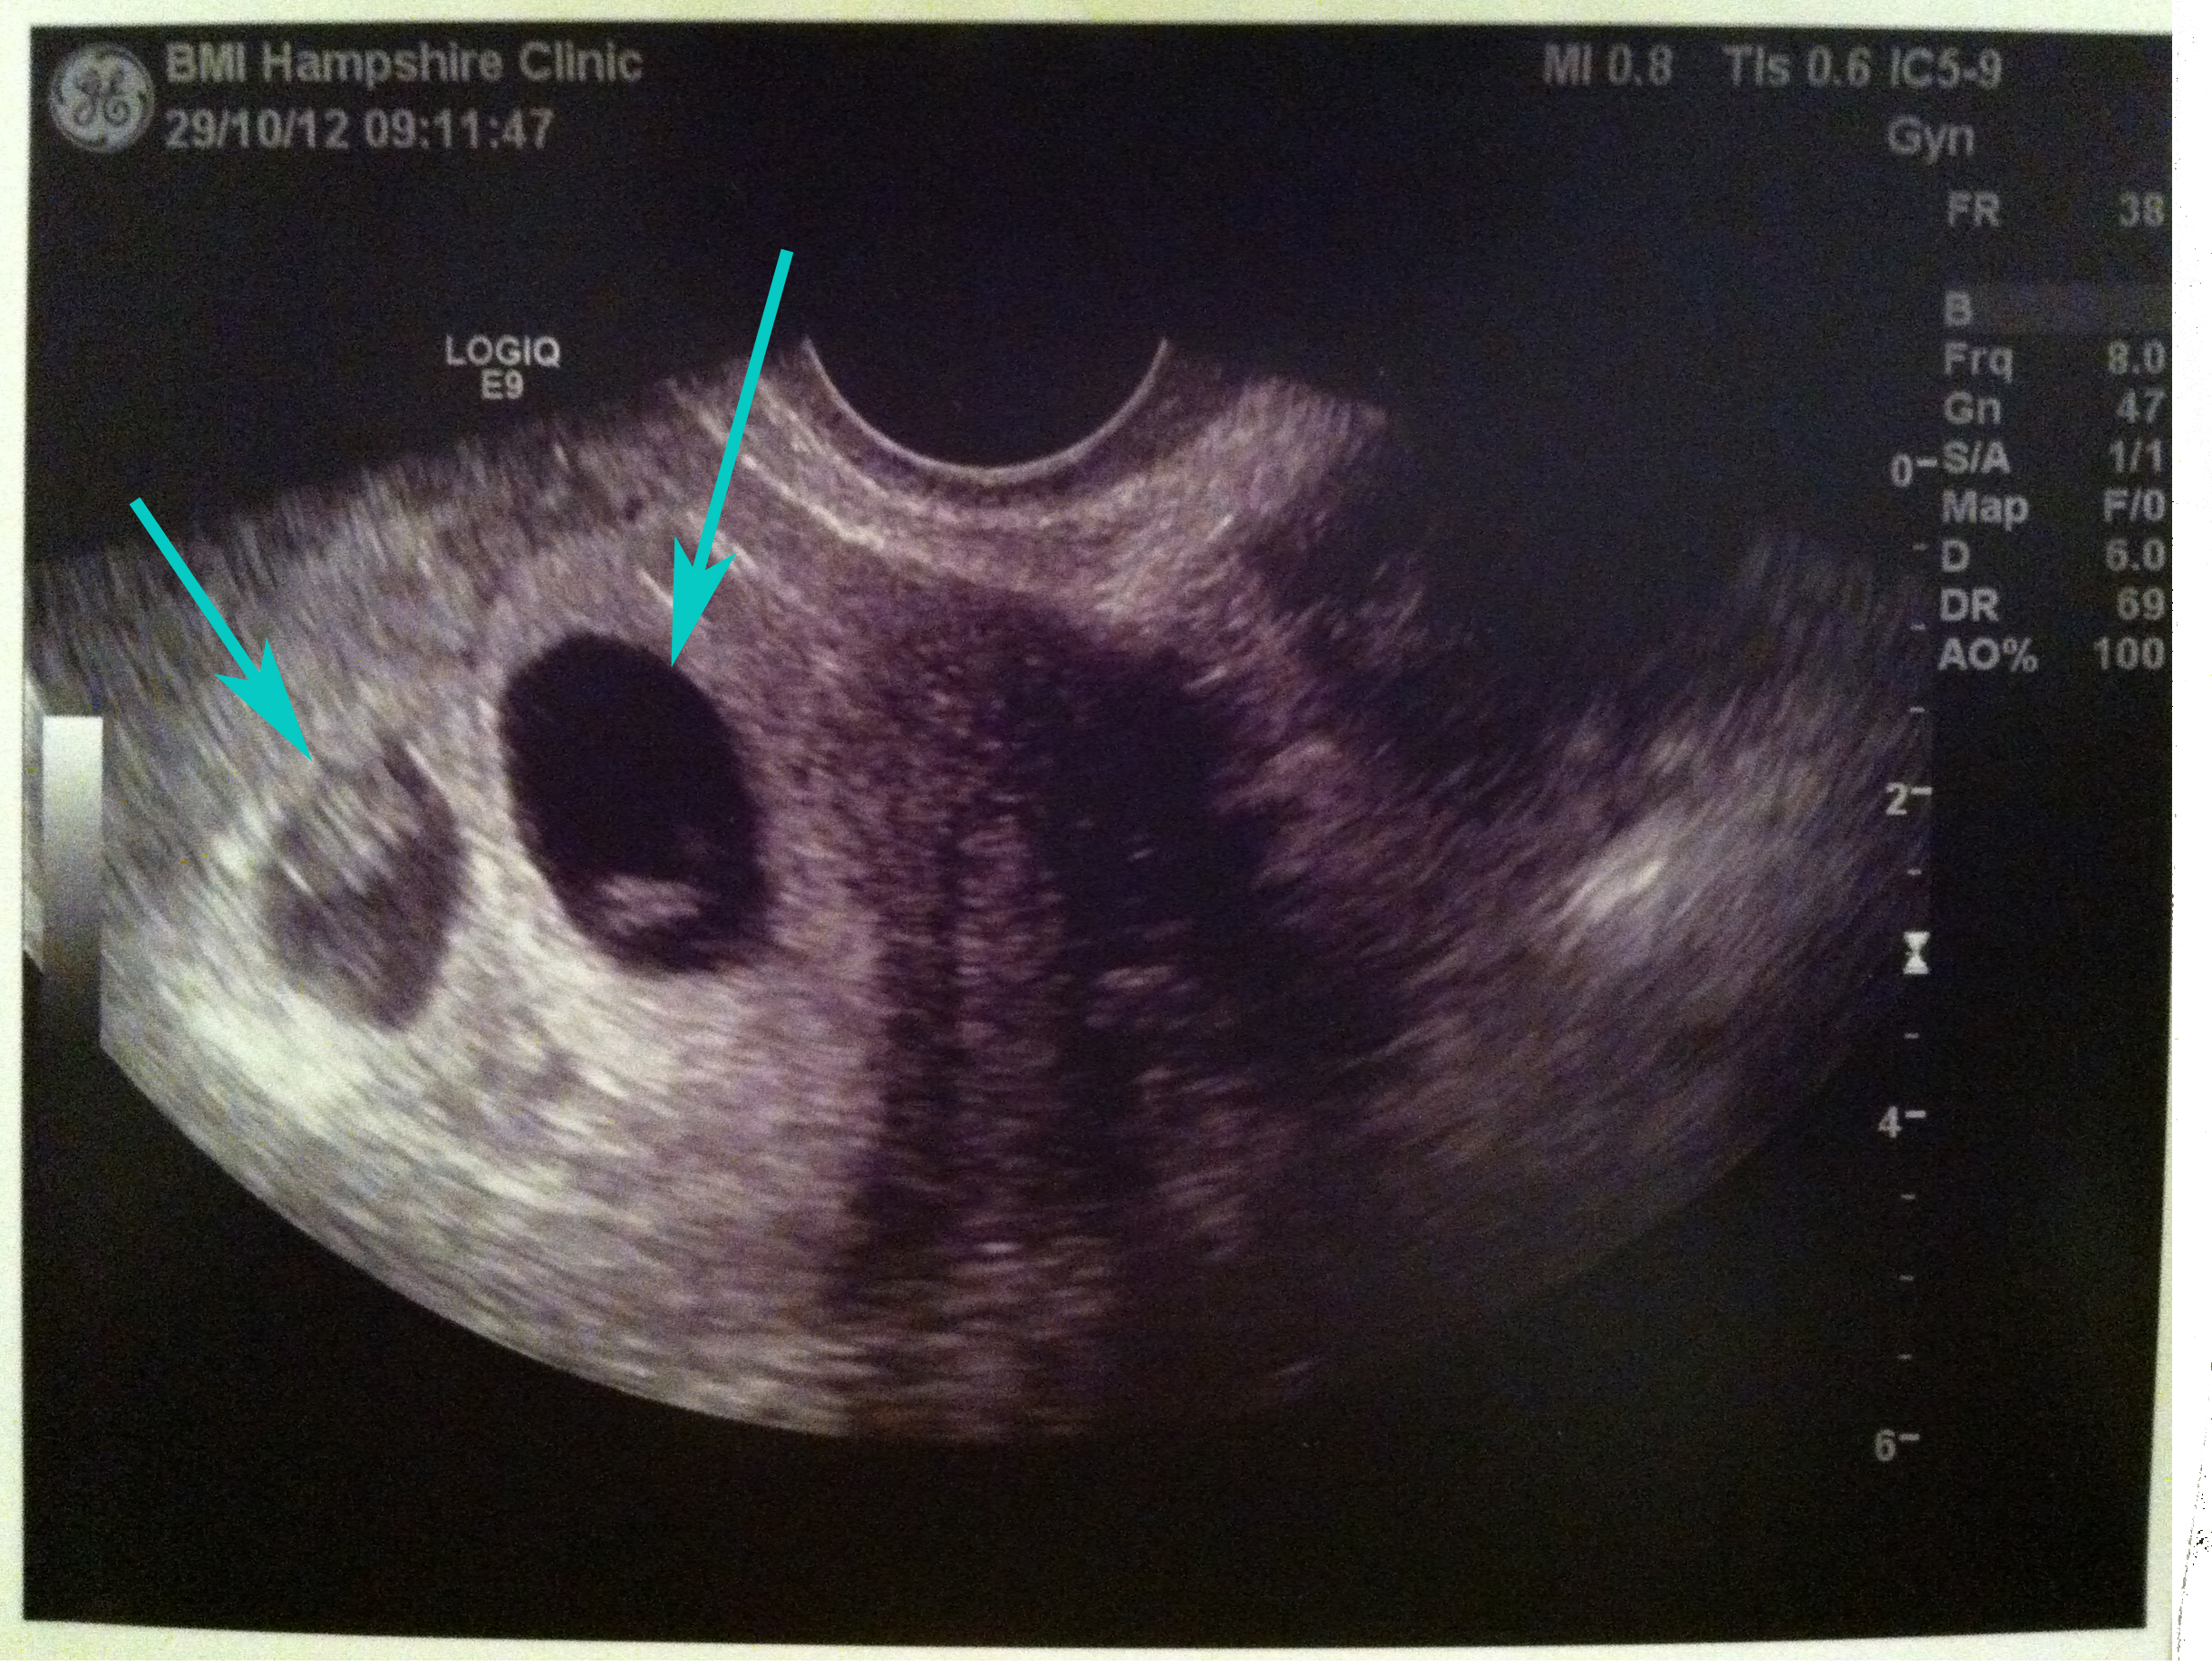

I had my first scan (internal) yesterday at the Hampshire Clinic. The main purpose was to see if there was a heartbeat and to measure the size of the embryo and the sack, were there one.

And although we had some suspicions (at the end of the day, they DID transfer two embryos), Jon and I had a great surprise to see two heartbeats!

The “bad” news is that one of those (the one on the left in the picture) is not as well developed as the other one, and Mr O’Sullivan said that he was going to sit on the fence for a while and wait to see how it keeps developing. I have another follow up scan in two weeks’ time to see how number two is doing.